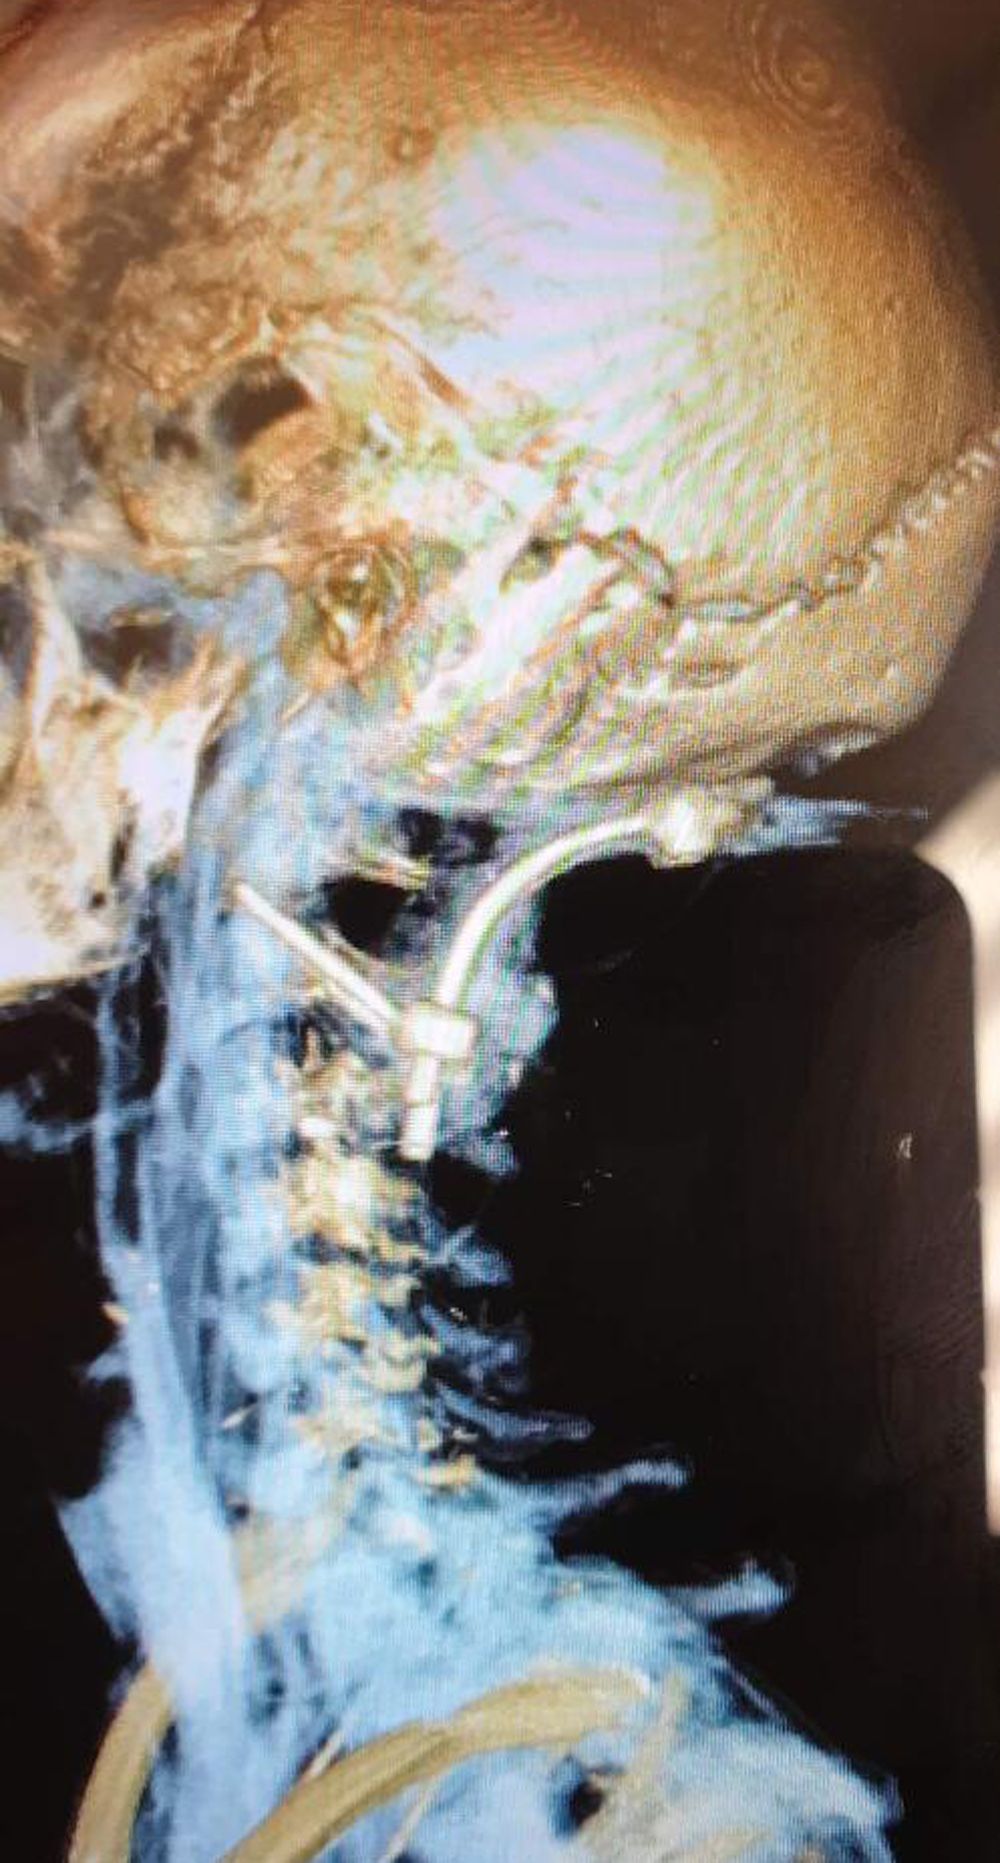

Unable to work and living in fear of her head detaching itself from her body, she has now launched a GoFundMe page, asking strangers to help raise £35,000 ($44,200) to fund surgery to fuse her C1 vertebra to the base of her skull, strengthening the area, restoring a full range of movement and giving Zoe her life back.

“A doctor in Barcelona, Spain, who is renowned for treating CCI and AAI, was recommended to me and backed up the diagnosis, telling me my only hope was to have surgery to fuse my neck to the base of my skull."

Last month, she found a clinic in Leeds, West Yorkshire, that can help—but she must raise £35,000 ($44,200), which she is hoping a GoFundMe page can help with. Meanwhile, until she can go under the knife, her life is virtually on hold.